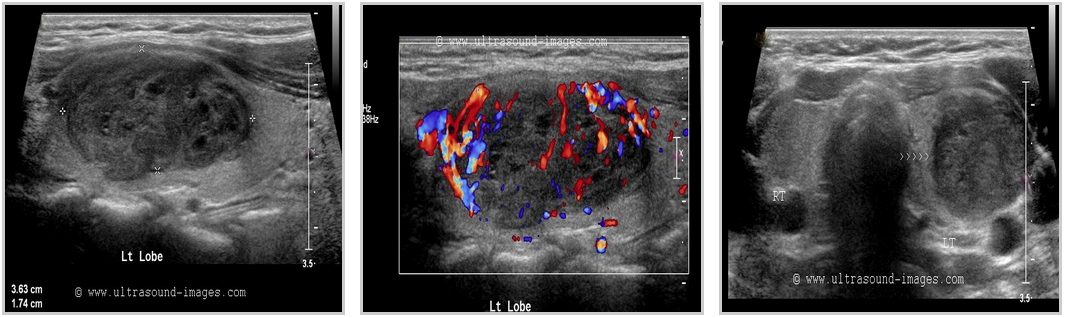

FOLLICULAR ADENOMAthyroid_follicular adenomas